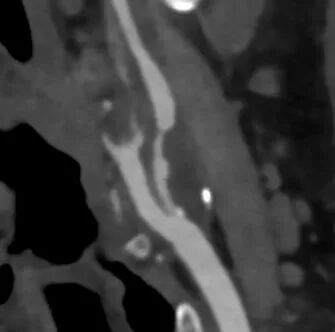

头颈联合CTA

-- 左侧颈内起始部重度狭窄,低密度斑块;右侧颈内及右侧椎动脉起始部中度狭窄;冠脉多发狭窄